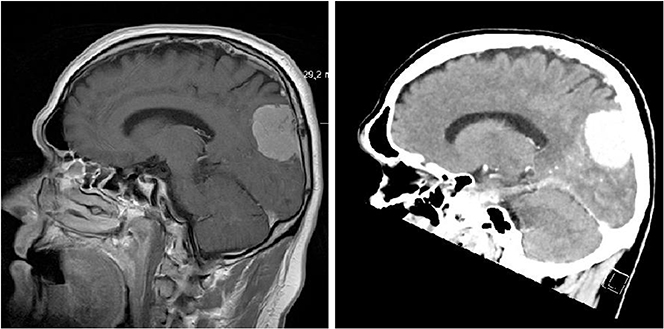

The potential of accelerator-reliant therapy and diagnostic techniques has increased considerably over the past decades, playing an increasingly important role in identifying and curing affections, such as cancer, that otherwise are difficult to treat; they also help to understand how major organs such as the brain function and thus to determine the underlying causes of diseases of growing societal significance such as dementia.